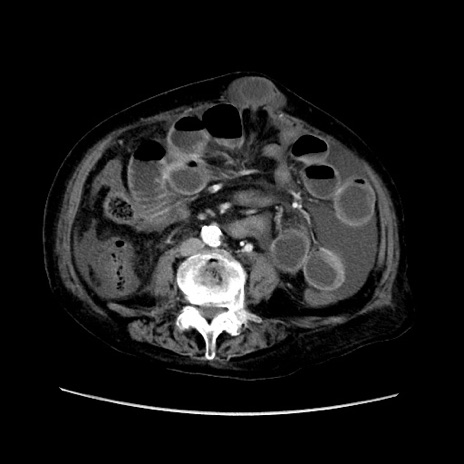

症例31(横断像)

【症例】80歳代 女性

【主訴】腹部膨満感

【現病歴】他院にて肝硬変にてフォロー中。1週間前から便秘、腹部膨満感、臍部腫瘤あり受診となる。

【既往歴】肝硬変

【身体所見】腹部膨隆あり、皮膚変化なし、疼痛なし。

【データ】WBC 4600、CRP 0.25